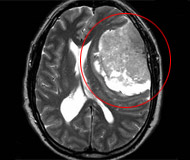

El desarrollo de nuevas tecnologías de imágenes junto a un mayor acceso, permite en la actualidad hacer un diagnóstico más precoz de estas lesiones, siendo fundamental la Resonancia Magnética y la Tomografía Axial Computada, los que en la gran mayoría de los casos son complementarias.

Efectivamente, es un tumor frecuente -corresponde a 1 de cada 4 tumores primarios del Sistema Nervioso Central- y es originado en las meninges, específicamente a nivel de las células aracnoidales, por lo que puede aparecer en cualquier sitio del Sistema Nervioso Central, tanto a nivel cerebral como de la columna vertebral. Además, suelen ubicarse entre el cerebro y la meninges, sin infiltrar los tejidos cerebrales ni espinales.

Pero, la localización más común, es en la convexidad cerebral (alrededor del cerebro) y en la Hoz (repliegue meníngeo que separa ambos hemisferios). En pocos casos, se ubica dentro de los ventrículos cerebrales o en estructuras meníngeas de la parte basal, en estrecha relación anatómica con nervios craneales y estructuras vasculares.